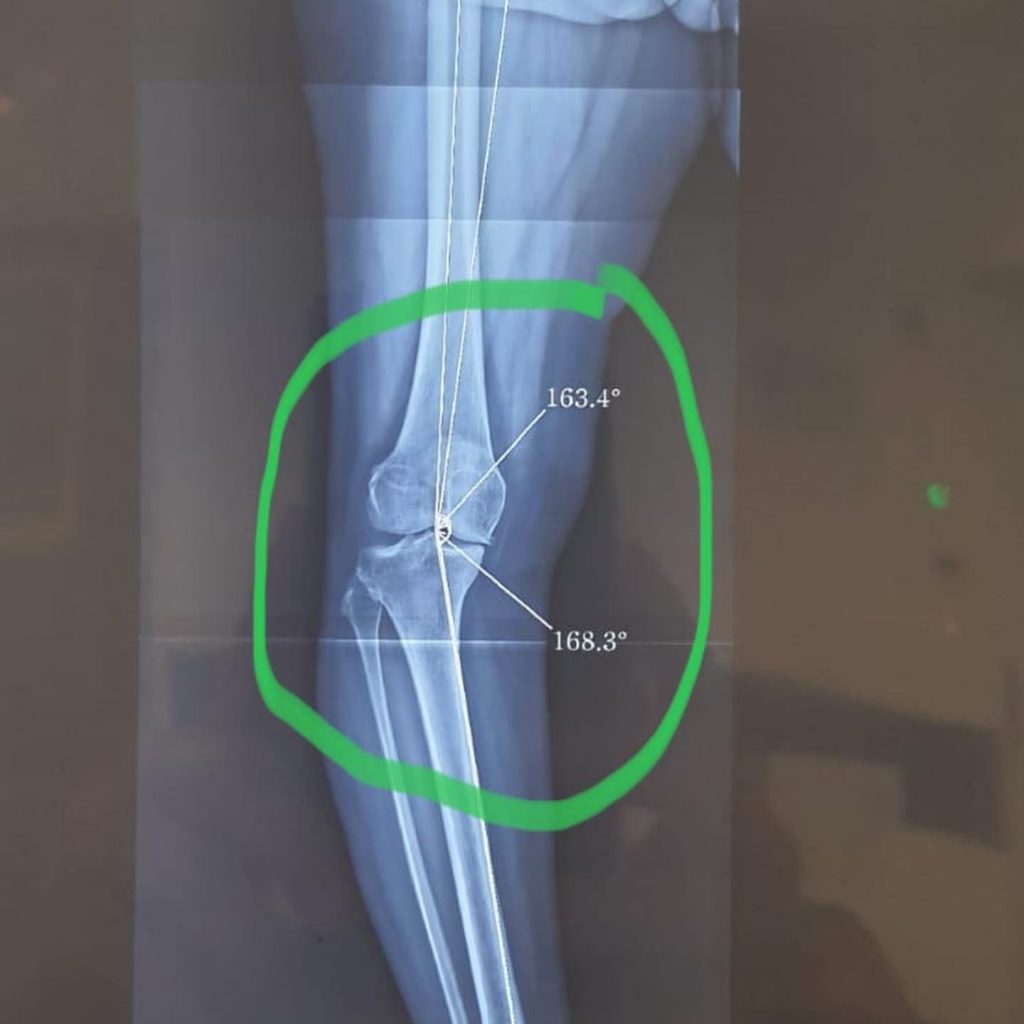

Essa paciente tinha a “perna cambota” nome popular para Deformidade em Varo além de uma artrose inicial.

Nosso especialista em Joelho Dr Danilo Lobo @daniloslobo realizou cirurgia Osteotomia Corretiva valgizante com placa, que é a correção do eixo da perna e colocação de placa.